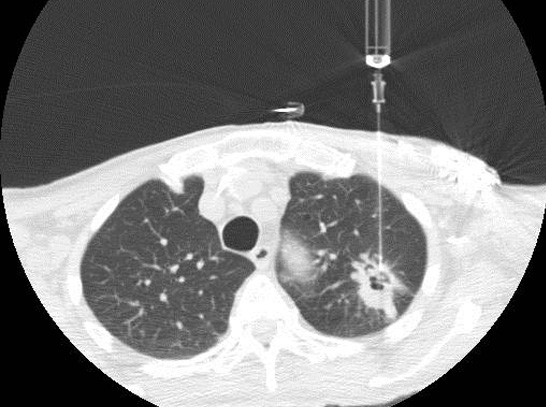

Santosham Chest Hospital offers CT Guided biopsies. Dr. Roy Santosham our Interventional Radiologist is an expert in CT guided Biopsies, Radio Frequency Ablation for inoperable tumors, Vertebral Biopsy, Vertebroplasty, Nerve root and Facet injections and Coeliac plexus block for pain relief.

A CT Guided Biopsy is a way of obtaining a small piece of tissue from an area that looks potentially abnormal. We use the CT Scanner to guide us to the right area to obtain the tissue. The CT Scanner is a machine, which uses X-rays and a Computer to produce a series of cross sectional pictures through the patient. These scans show much more detail than can be appreciated on an ordinary X-ray picture. Most people having a biopsy will have had a CT Scan already but for those who have not, the CT Scanner is a large square box with a big round hole through it’s middle, rather like a huge square donut or polo mint. The patient being scanned lies on a table, which passes through the hole in the machine the table is then positioned so that the area being scanned is in the centre of the hole.